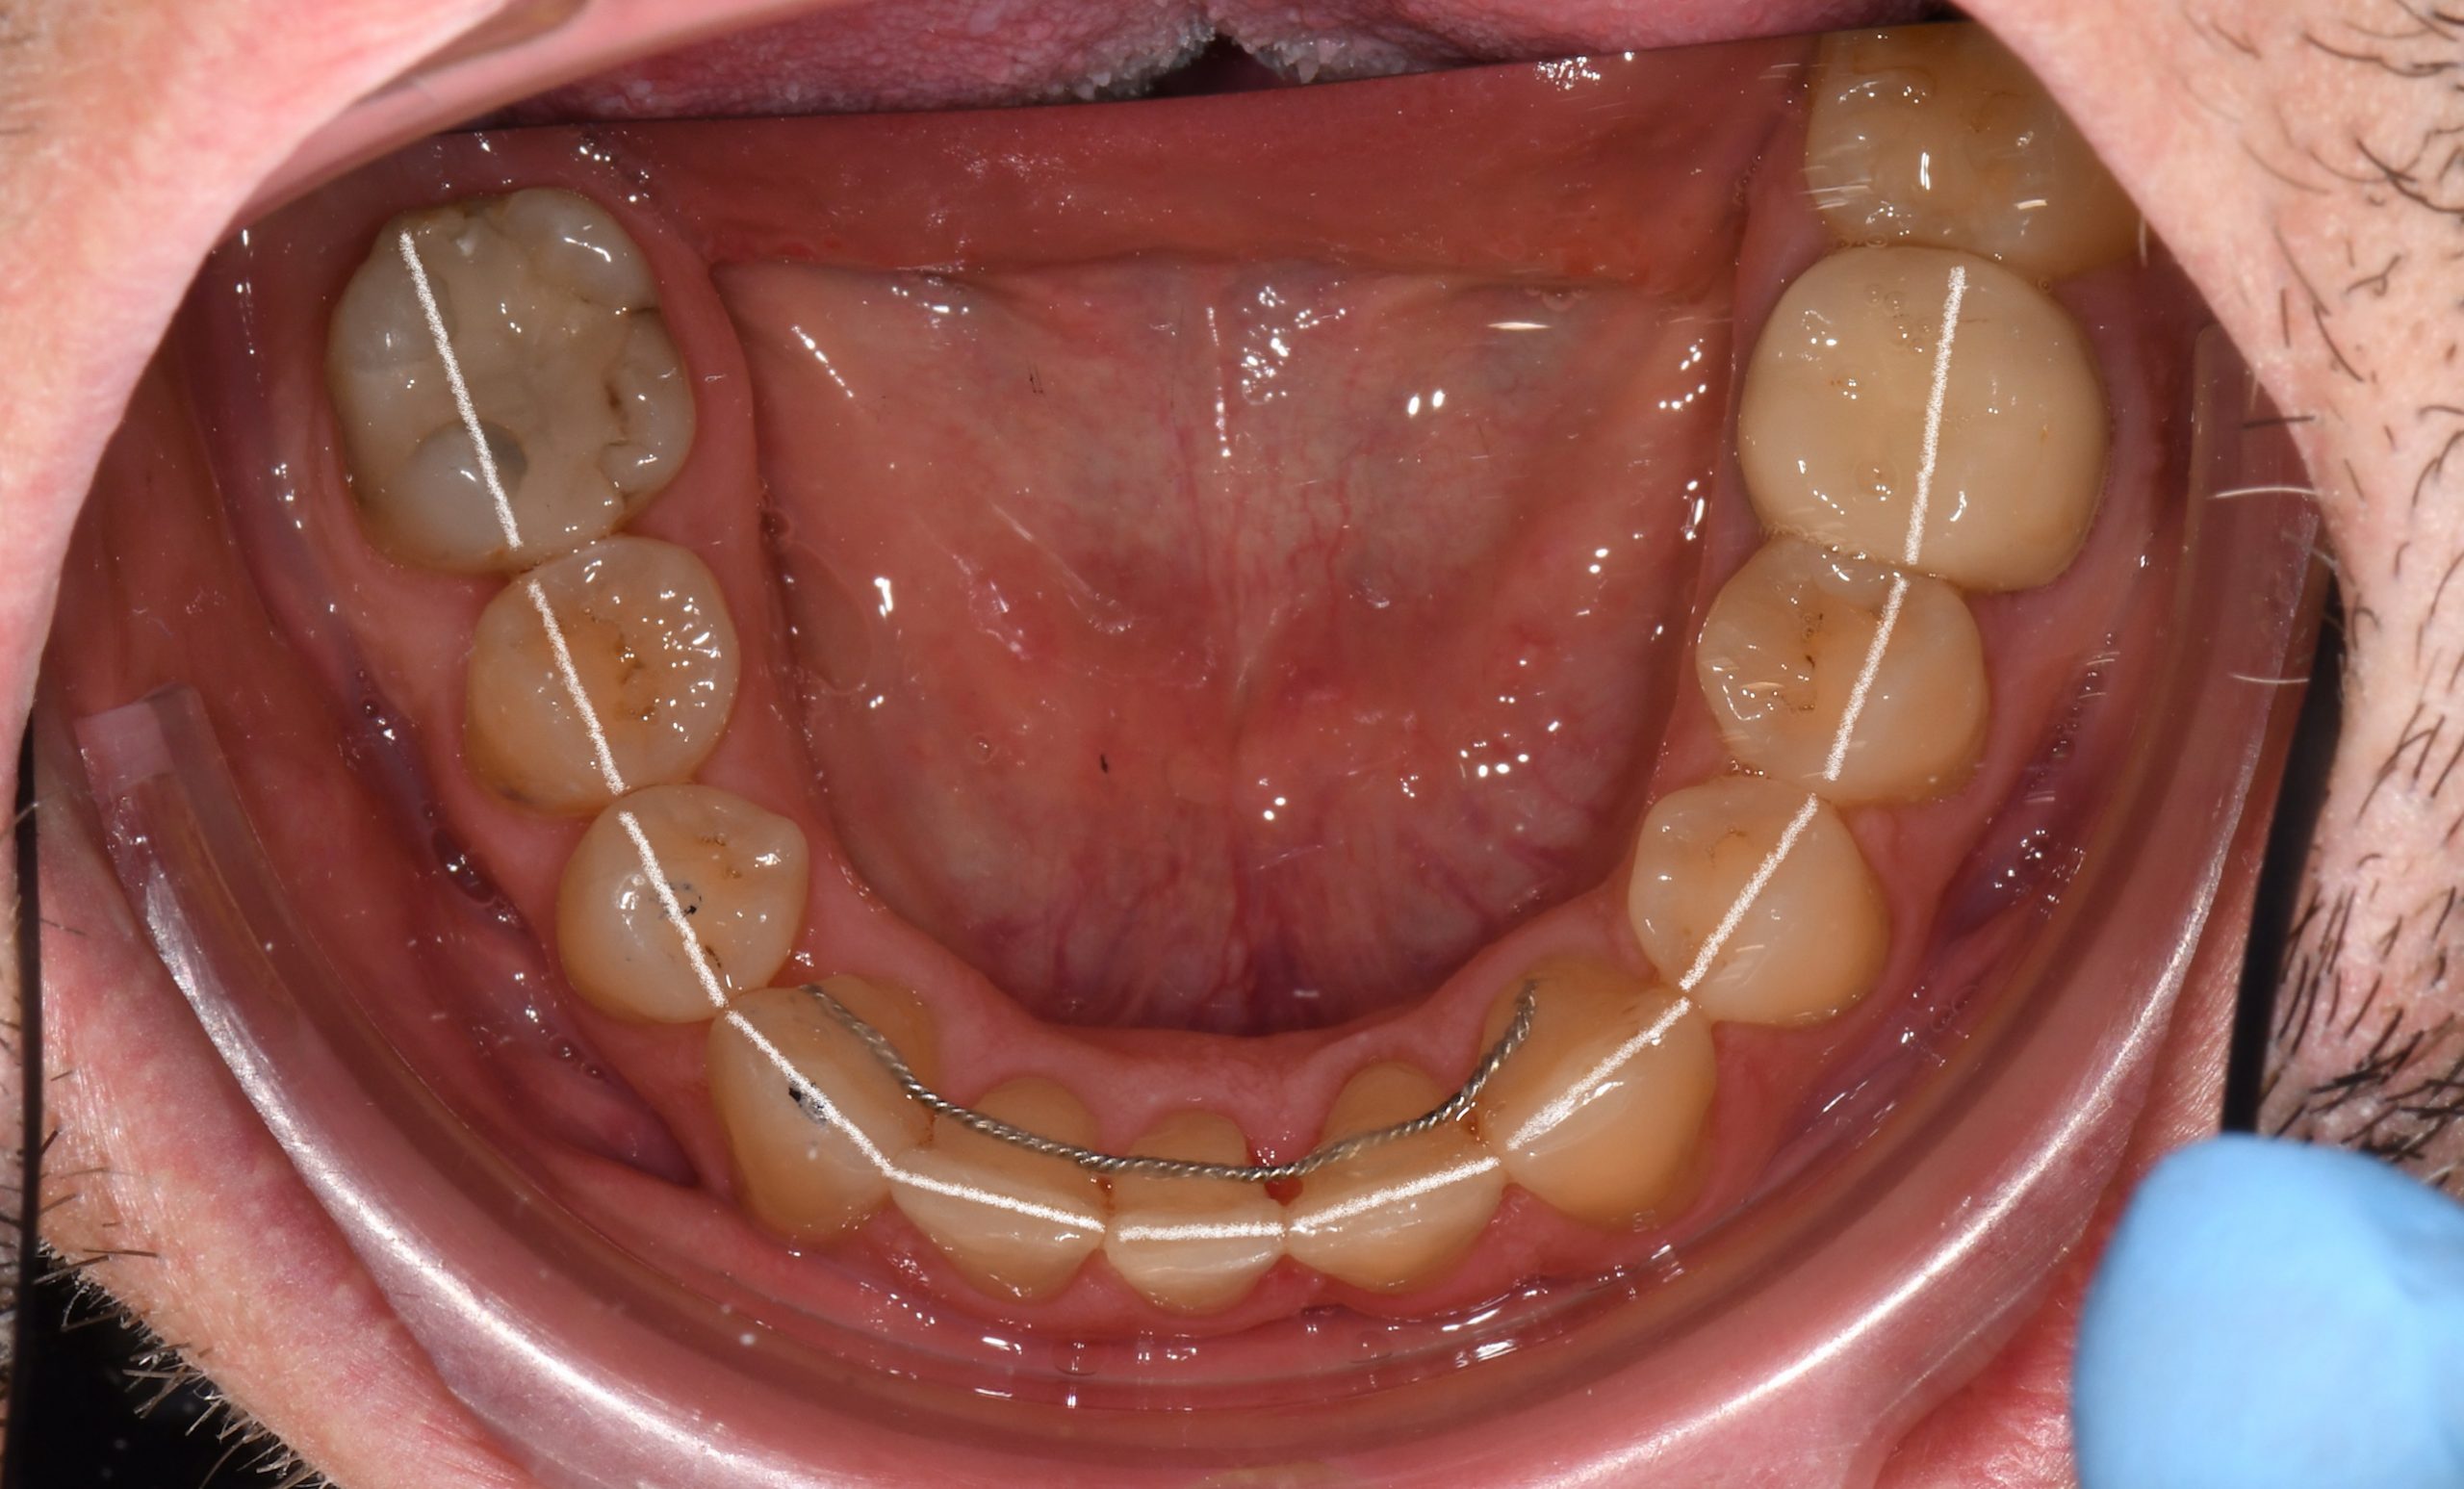

Az elmúlt évekből rengeteg szakmai referenciát tudnánk bemutatni, amelyek különböző fogszabályozási problémákat oldottak meg. Válogatva a több száz esetből, ezen az oldalon olyan képeket, információkat igyekeztünk bemutatni, amelyeknek a segítségével a jövőbeni pácienseinknek azt tudjuk üzenni: A Te fogsorod is lehet gyönyörű!

(Képeket a Pácienseink külön írásos beleegyezésével mutatjuk be!)